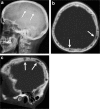

Calvarial lesions are often asymptomatic and are usually discovered incidentally during computed tomography or magnetic resonance imaging of the brain. Calvarial lesions can be benign or malignant. Although the majority of skull lesions are benign, it is important to be familiar with their imaging characteristics and to recognise those with malignant features where more aggressive management is needed. Clinical information such as the age of the patient, as well as the patient's history is fundamental in making the correct diagnosis. In this article, we will review the imaging features of both common and uncommon calvarial lesions, as well as mimics of these lesions found in clinical practice. TEACHING POINTS: • Skull lesions are usually discovered incidentally; they can be benign or malignant. • Metastases are the most frequent cause of skull lesions. • Metastatic lesions are most commonly due to breast cancer in adults and neuroblastoma in children. • Multiple myeloma presents as the classic "punched out" lytic lesions on radiographs. • Eosinophilic granuloma is an osteolytic lesion with bevelled edges.